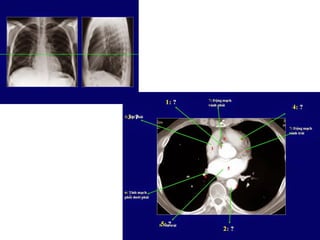

Giải phẩu CT ngực – các mạch máu

lớn.

SVC: tĩnh mạch chủ trên.

Aortic arch: cung đm chủ

Pulmonary artery: đm phổi

Main sterm bronchus: phế quản gốc

63